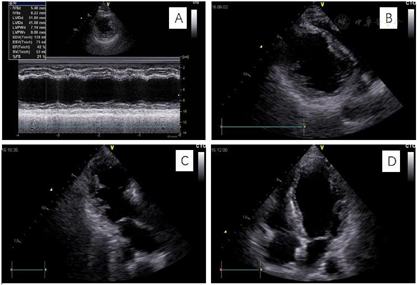

(1)外院心电图示:室性心动过速、ST-T改变(图1)。(2)外院动态心电图之一(1996年6月4日):平均心率77次/min,最快129次/min,最慢56次/min;见个别室早<64次;"RonT"、"插入性室早"、"室早成对"、"室性心动过速"等均系伪差干扰电脑误判,无ST-T改变(监护23 h)。(3)外院动态心电图之二(2019年8月6日):平均心率64次/min,最快94次/min,最慢52次/min;室性早搏936次,有1次成对室早,49阵室性二联律,无室性心动过速;房性早搏9个(4)上海交通大学医学院附属瑞金医院心电图(图2):QRS时限短,T波低平,I、avL肢导低电压。(5)胸X线:两肺纹理略多,未见确切活动性病变。(6)超声心动图(图3):心腔大小及厚度:左房内径33 mm,左室舒张末期内径52 mm,左室收缩末期内径41 mm,室间隔厚度6.5 mm,左室后壁厚度7.5 mm。二维:左室偏大,左室壁不增厚且心肌厚度不均匀,心尖处最薄,部分区域心肌组织较疏松。静息状态下左室壁各节段收缩活动减低,尤以心尖部最明显。各心瓣膜未见明显增厚,开放不受限。右室壁未见明显变薄。左心功能测定:左室舒张末期容量118 ml,左室收缩末期容量63 ml,左室射血分数46%,左室短轴缩短率23%,每搏输出量55 ml。结论:左室壁心肌厚度不均匀,心尖处较薄,部分区域心肌组织较疏松,综合考虑心肌病可能较大。(7)为进一步明确病因,完善冠状动脉造影,结果提示大致正常(图4)。(8)CMR:左室壁心肌厚度不均,左室前壁及心尖处较薄,增强后左室前壁心内膜下可见片状强化,未见反常运动和矛盾运动,左室射血分数41%。结论:左室壁心肌厚度不均匀,左室功能不全,提示非缺血性心肌病变(心肌致密化不全可能,图5)。